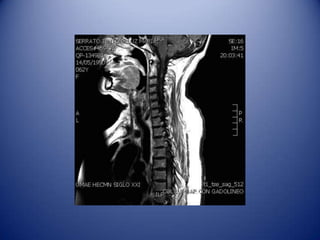

MRI: Hyper intensity with T1

enhancement, suggestive of

longitudinal myelopathy

From C2 to T12 with high activity in

Case: Female, 62years old.  2001: Optic Neuritis in right eye.  2010: Non Hodgkin lymphoma, QxTx RxRx.  May 2010: Optic Neuritis in left eye. Hypotiroidism. ANA 1:640 H, lymphopenia, leukopenia, Neurolupus: Pdn 50mg/d and Mycophenolate.  Oct 3 2010: Hyperstetic sensitive level C5 and T7, medular discharges, hyporeflexia.

• 45.

Oct 3 2010:Hyperstetic sensitive level C5 and T7, medular discharges, hyporeflexia. MRI: Hyper intensity with T1 enhancement, suggestive of longitudinal myelopathy From C2 to T12 with high activity in neuro-imaging